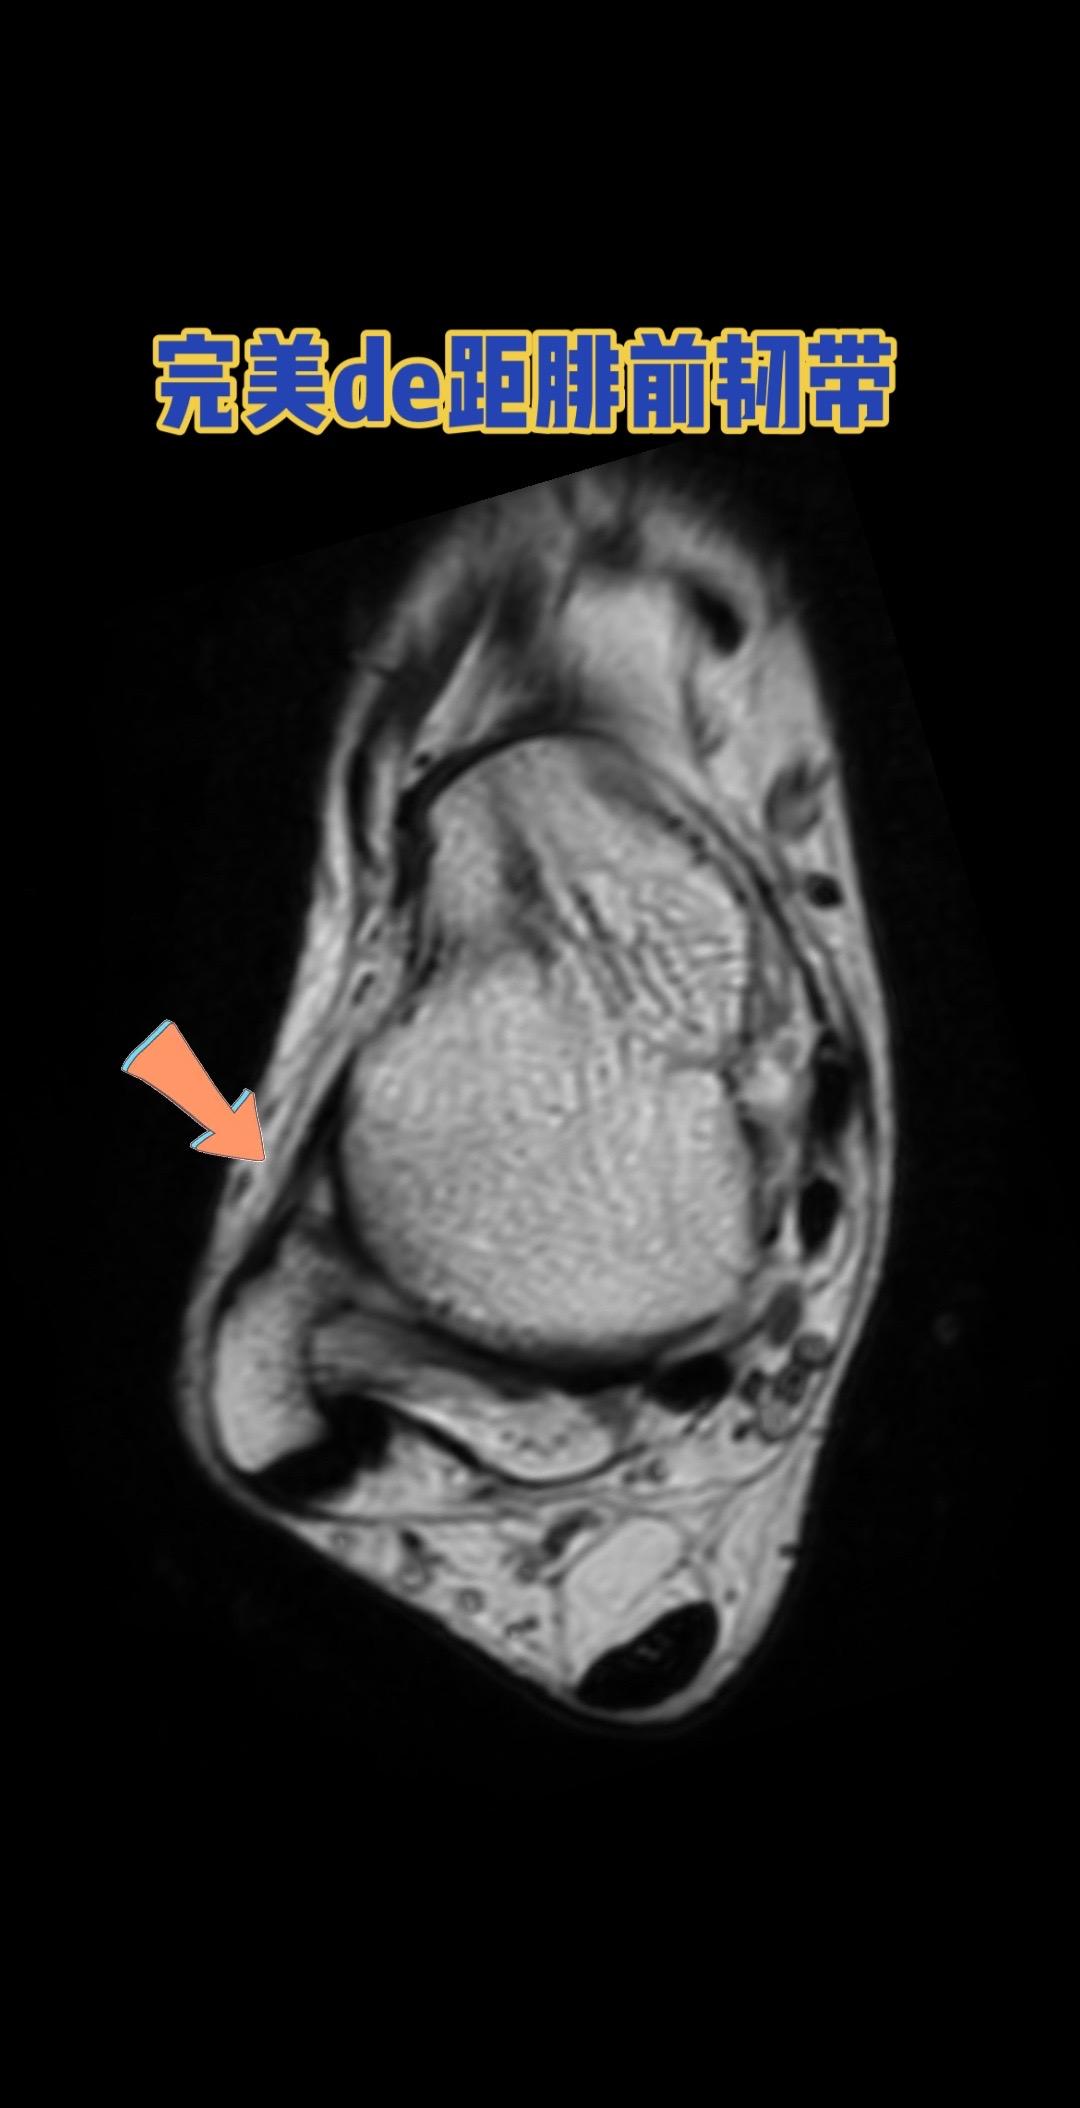

距腓前韧带。👉 健康的距腓前韧带长这样! 距腓前韧带

距腓前韧带。👉 健康的距腓前韧带长这样!